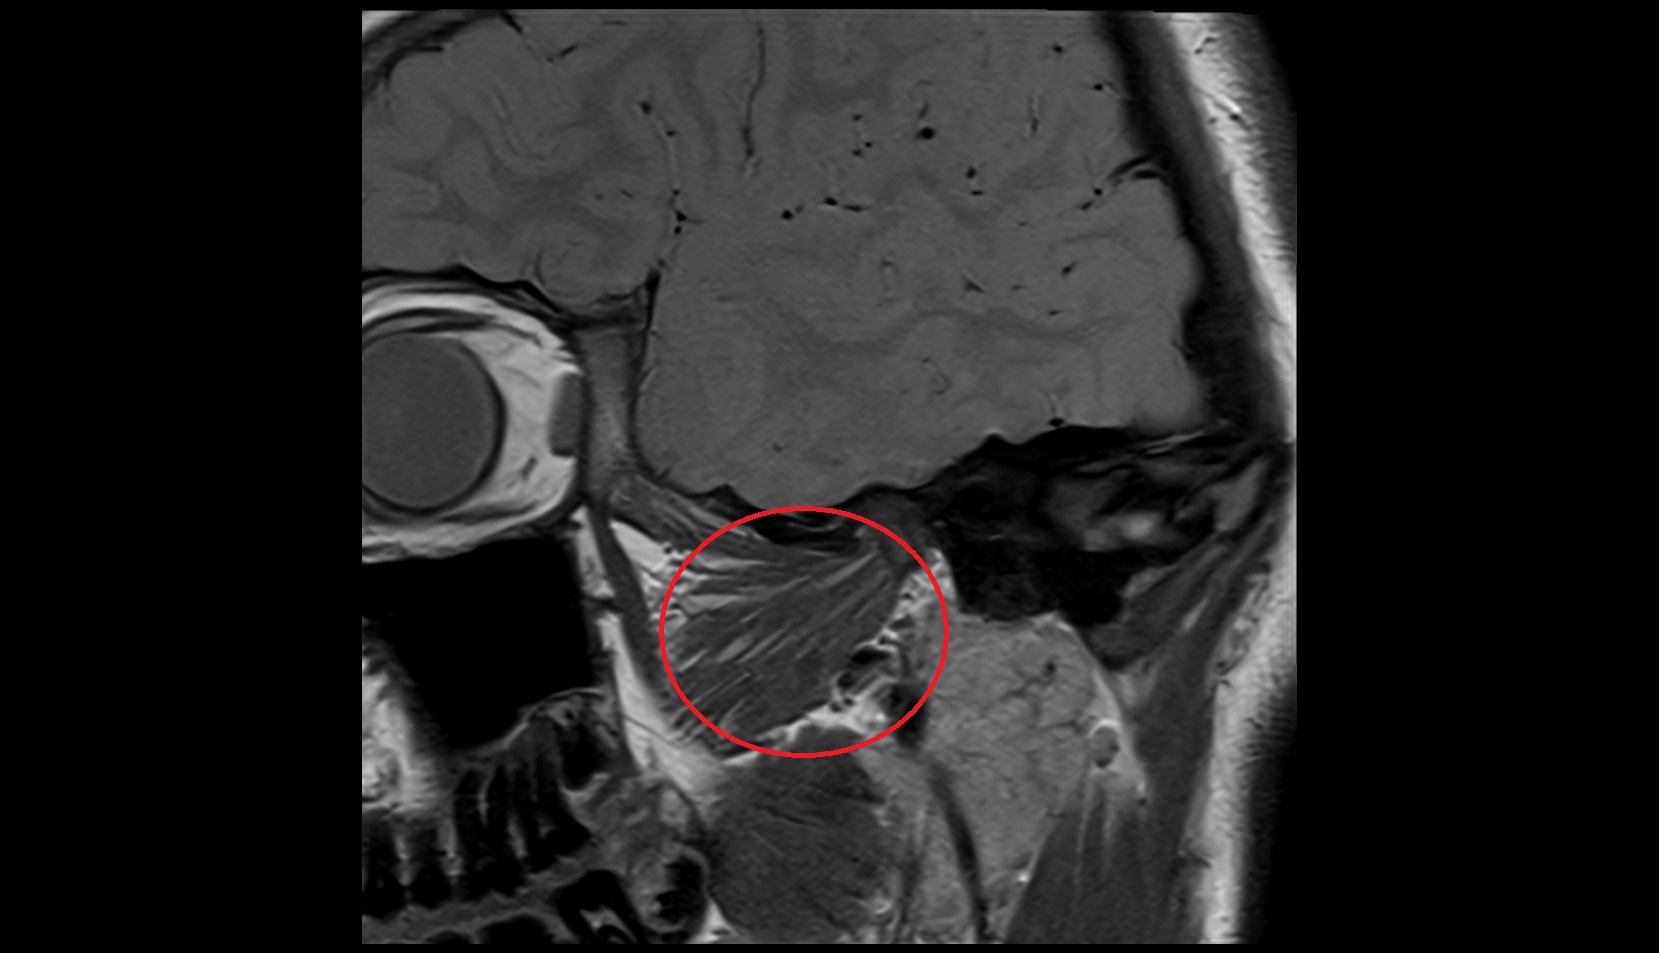

- Temporomandibular joint

- Articular disc of temporomandibular joint

- Articular eminence

- Mandibular condyle

- Mandibular fossa